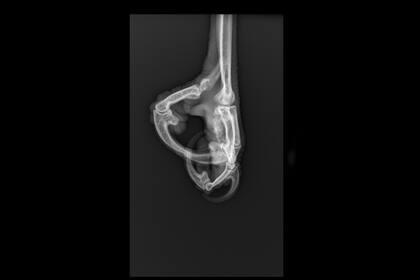

Como primera medida se le tomaron radiografías para saber si tenía algún compromiso óseo. Además de evaluar la herida de la pata derecha, los veterinarios observaron que tenía un cuadro de pododermatitis infecciosa en ambas almohadillas de las garras, una inflamación que se produce por el contacto permanente con un sustrato inadecuado, en este caso presumiblemente un caño o algo rígido.